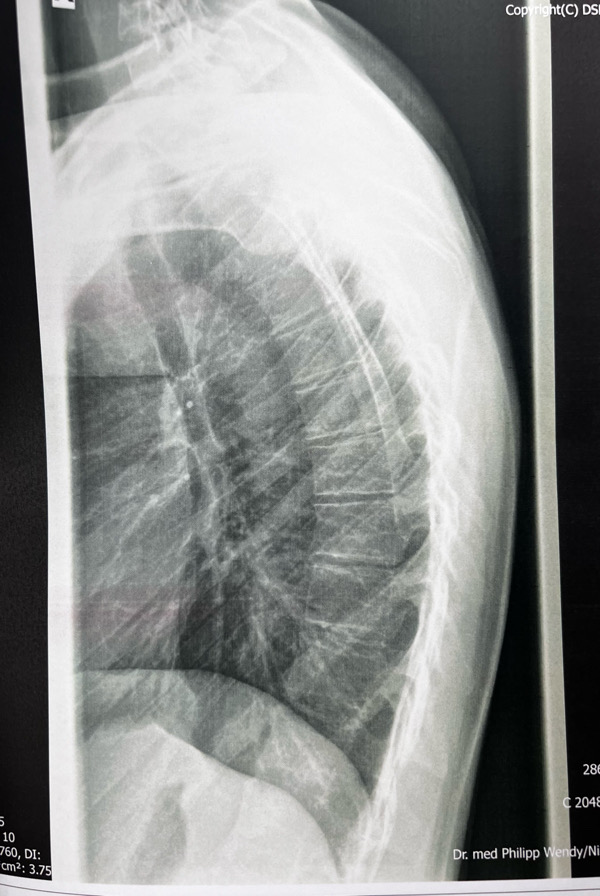

heute war ich nochmal bei meinem Orthopäden und habe die Röntgenbilder abgeholt. Ich wollte wissen, wo und ob ich wirbelveränderungen habe, weil der Orthopäde sich nicht wirklich bei meinem Termin dazu geäußert hat. Leider konnte mir bei der Rezeption niemand helfen und es wurde nur gesagt, wahrscheinlich leicht.

Ich dachte ich stelle hier nun mal die Bilder ein. Einmal von der Seite und von vorne. Der Bericht mit der Diagnose ist auch dabei. Kann jemand anhand der Röntgenbilder offensichtliche Keilwirbel erkennen und vielleicht auch grob was zu dem Kyphosewinkel sagen. Ich selber glaube Ansätze von keilwirlbel zu sehen, aber ich bin mir nicht sicher.

Musste die Aufnahmen von der Qualität etwas verkleinern, da ich sie sonst nicht hätte einfügen können.

Die Messung vom BWS Kyphosewinkel erfolgt mittels der sogenannten Neutralwinkel, das sind die Wirbel am Wendepunkt zur HWS Lordose und der LWS Lordose. Der HWS Übergang ist schwer zu sehen und der LWS Übergang kaum sichtbar, weil es nur eine BWS Aufnahme ist.

Deshalb sollte immer eine Röntgen-Ganz-Aufnahme (LWS, BWS und HWS) gemacht werden. Frau Dr. von Ricthofen kann solche Aufnahmen machen. Grob kann ich nur sagen, dass die in der Diagnose erwähnte "vermehrte Kyphosierung" bzw. später im Text "leicht vermehrte Kyphosierung" nachzuvollziehen ist.

Es sieht für mich aber so aus, als ob der obere Kyphosebogen zu flach ausgeprägt ist.

Also grundsätzlich finde ich die Beantwortung dieser Fragen problematisch, weil das den Ärzten bzw. den Spezialisten vorbehalten ist und Dich aktuell auch gar nicht weiterbringen würde.Kann jemand anhand der Röntgenbilder offensichtliche Keilwirbel erkennen und vielleicht auch grob was zu dem Kyphosewinkel sagen

Zu Keilwirbel kann ich nur sagen, dass die in der Regel an der Behandlung nichts ändern. Es kann je nach Anzahl und Lage dieser Wirbel u.U. die Behandlung mehr oder weniger beeinflussen.

Ich habe mir deine Bilder angeschaut. Da ich selber zig Bilder analysiert und mit Software ausgemessen hab, kann ich dir folgendes mitteilen:

- Der globale Cobb-Winkel, definiert als der Winkel zwischen dem meist geneigten BWS-Wirbel im unteren Segment (das ist häufig T11 oder T12) und dem meist in-die-andere-Richtung-geneigten BWS-Wirbel im oberen Segment (T1 bis T4 häufig) kommt bei dir auf ca. 55 Grad zu belaufen.

- Manchmal wird auch implizit der Stagnara-Winkel gemessen, und als Cobb-Winkel ausgewiesen. Dieser ist strikte definiert als der Winkel zwischen T4 und T12 und wird häufig angewendet, weil die oberen Wirbel (T1 bis T3) auf dem Bild nicht klar ersichtlich sind. Da ich nicht genau identifizieren kann, welcher Wirbel welcher ist, kann ich es nicht genau sagen, ich schätze aber auch hier, dass 42 Grad zu tief bemessen ist.

- Viele deiner BWS-Wirbel sind milde verkeilt (zwischen 5 und 10 Grad). Man spricht von Keilwirbel ab 5 Grad. Das ist nicht sonderlich viel und wird leider von vielen Docs/Spezialisten komplett übersehen. Wenn mehrere Wirbel betroffen sind, führt das aber sehr schnell zu einer strukturellen Verkrümmung, genau so wie in deinem Fall.

- Die einzige Bedingung, die für eine Diagnose des klassischen Morbus Scheuermann erfüllt sein muss, ist, dass drei oder mehr aufeinander folgende BWS-Wirbel eine Keilform von 5 Grad oder mehr haben. Daneben gibt es eine Reihe von radiologischen Eigenschaften, welche alle auf einen Morbus Scheuermann hinweisen bzw. gehäuft mit diesem in Erscheinung treten, nicht aber notwendig für die Diagnose sind: Schmorl-Knoten, Grund- und Deckplatten-Unregelmässigkeiten, verschmälerte Zwischenwirbelräume, globaler Cobb-Winkel von mehr als 40/50 Grad (je nach Quelle und Messmethode).

- Der Cobb-Winkel ist aus diversen Gründen mit Vorsicht zu interpretieren: Es wird keine Unterscheidung zwischen struktureller Verkeilung von Wirbelkörpern und Bandscheiben (z.B. weil sie asymmetrisch degeneriert sind) und der physiologischen Verkeilung/Verformung von Bandscheiben bei z.B. einer Haltungsschwäche gemacht. Es wird einfach alles addiert. Es versteht sich von selbst dass der Grad der Unsicherheit hier enorm sein kann. Darum ist vor allem der Grad der individuellen Verkeilung der Wirbelkörper entscheidend. Ein MRI gibt zudem Aufschluss über den Zustand der Bandscheiben, und ob es bereits zu einer frühen Degeneration gekommen ist.